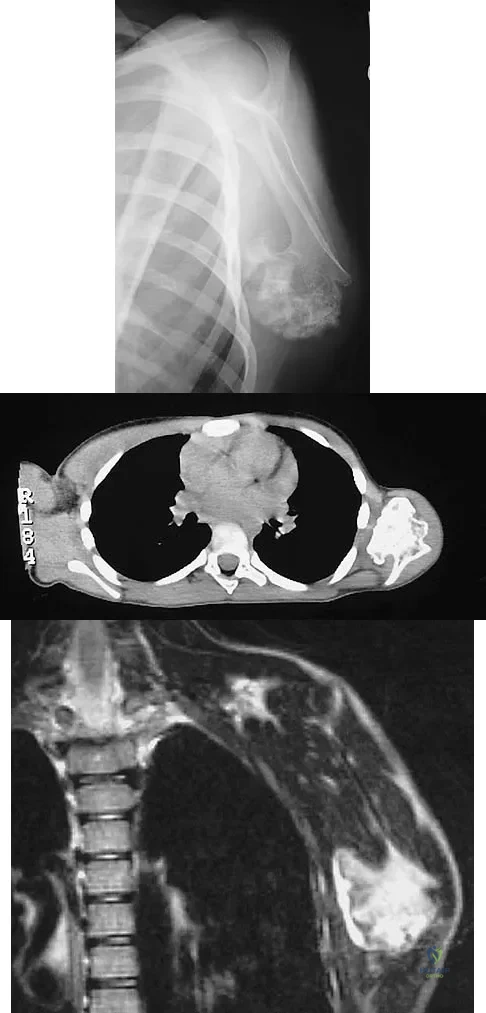

A 12-year-old boy has severe left shoulder pain after being struck by an automobile. A chest radiograph, AP and lateral radiographs, and a CT scan with three-dimensional reconstruction of the scapula are shown in Figures 38a through 38d. Management should consist of